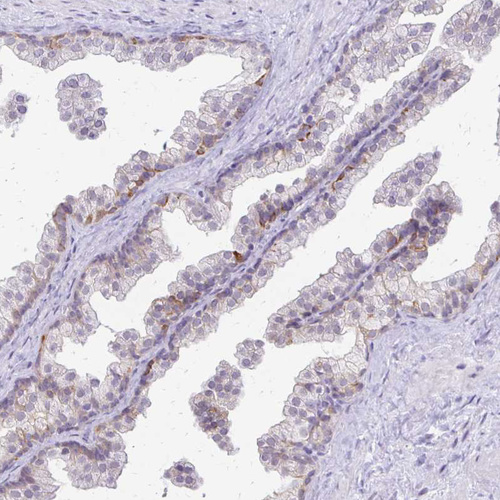

Immunohistochemical staining of human placenta shows moderate cytoplasmic positivity in decidual cells and strong positivity in trophoblast.